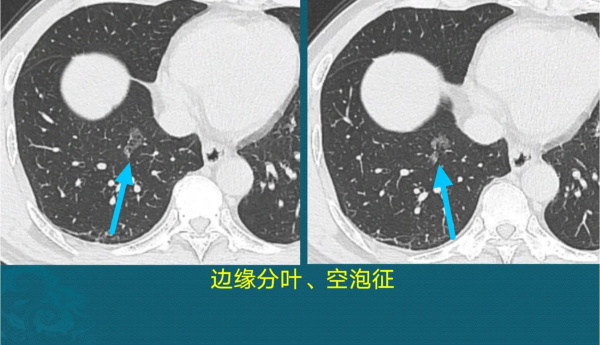

磨玻璃结节常见的恶性征象有:空泡征、分叶征、胸膜凹陷征、支气管充气征、支气管截断征、血管穿行征(伴有血管增粗、僵直、模糊等改变)。

比如这个1.5cm的结节,边缘像树叶一样分叶,内部有几个黑色小泡(空泡征),他间隔数月复查结节未吸收,果断做了手术,病理是原位腺癌(1.5cm的原位癌较少见,>1.5cm的多为浸润性腺癌)。

简单解释一下空泡征,在早期肺癌内部,由于癌细胞浸润,肺泡间隔弹性减退、崩塌,相邻的肺泡腔融合,形成肉眼可见的小气腔(<5mm)。该征象大约见于50%的早期肺腺癌,但也有约5%的炎症性结节可以出现空泡征,需要综合分析。